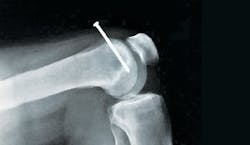

The first time Shawn Mahler nailed through bone happened while shooting sole plates into a subfloor. He ran out of hose, so he gave the nail gun a yank. That pulled his hand down, pushing the gun tip into his boot. The result was a nail through the foot—the picture below is the X-ray Mahler got in the emergency room before they yanked the nail. He lost a month of work.